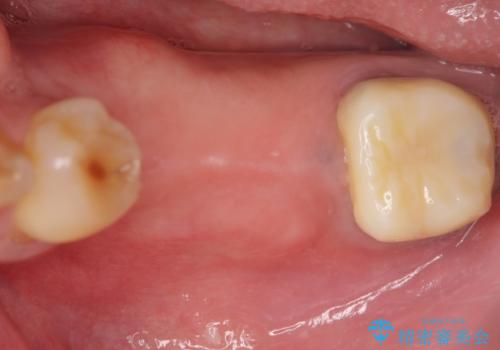

- 左下奥歯が虫歯で抜歯になってしまったため、インプラントにしたいといらっしゃった方の症例です。

欠損部位である左下5、6番目にインプラントを埋入し、オールセラミッククラウンによる補綴を行いました。